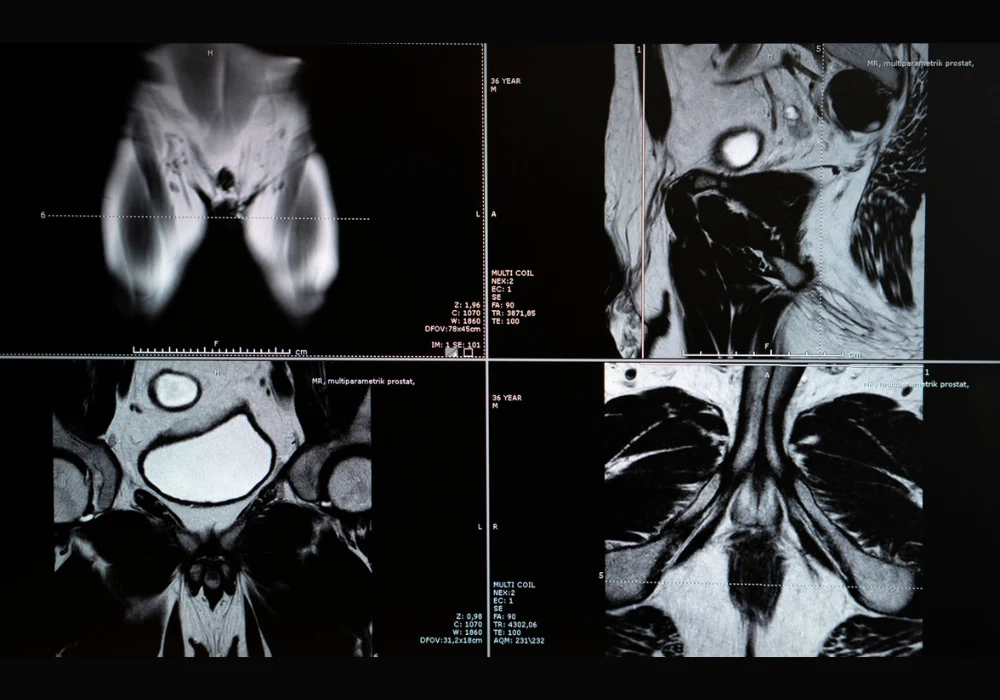

Prostate cancer remains one of the most prevalent malignancies affecting men worldwide and poses a major burden on health systems. While biparametric MRI is recommended as a primary diagnostic approach, its standard assessment method—PI-RADS—has limitations, particularly a high false-positive rate. These limitations often result in unnecessary biopsies, with implications for patient safety and resource utilisation. To address this, a multimodal machine learning model was developed and validated across multiple centres to improve the prediction of clinically significant prostate cancer using imaging, clinical and radiomic features.

The multimodal model was trained using retrospective data from twelve clinical centres, incorporating T2-weighted, diffusion-weighted imaging and apparent diffusion coefficient sequences. It combined radiomic features, which quantify shape and texture, with clinical variables such as age, PSA levels, lesion location and PI-RADS scores. Radiomic extraction covered the entire prostate gland using segmentation masks generated by a deep learning model. Performance was assessed through retrospective and prospective datasets, ensuring temporal generalisability and robustness across scanner vendors and field strengths.

The model consistently outperformed PI-RADS in detecting clinically significant cases, defined as ISUP grade 2 or higher. Compared with PI-RADS, the model achieved a higher AUC and specificity in both retrospective and prospective cohorts. At the same sensitivity level, the model reduced unnecessary biopsies by more than 20%, and at the same specificity, it detected more cases of clinically significant cancer. SHAP analysis confirmed that radiomic features, alongside PI-RADS and lesion location, significantly contributed to prediction performance.